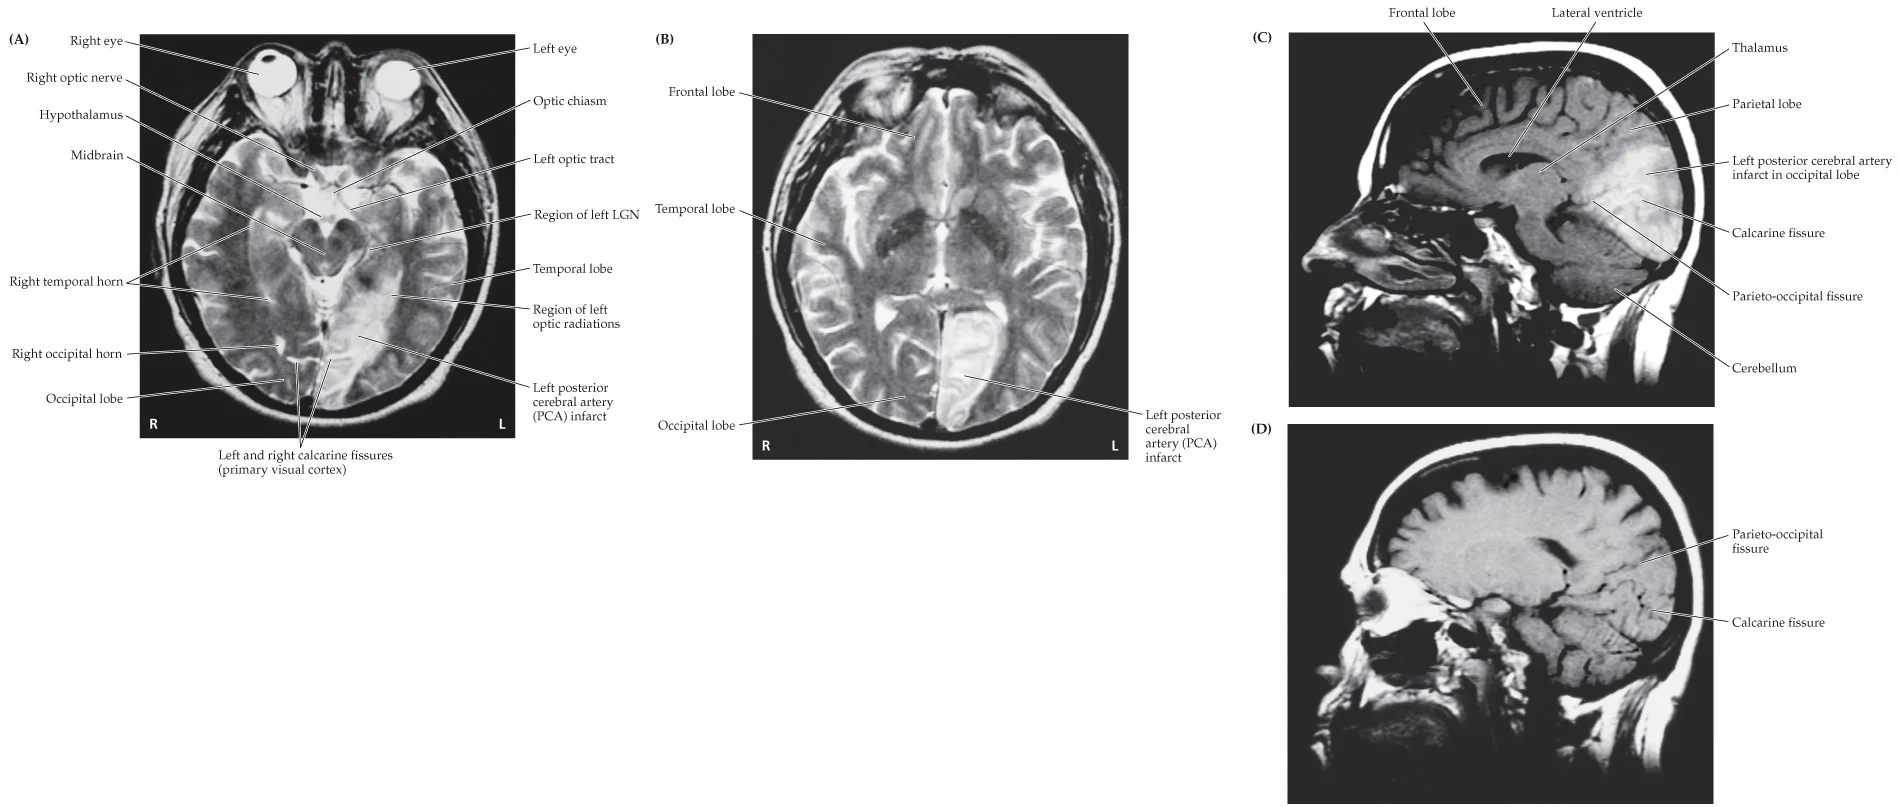

A 63-year-old woman went to an ophthalmologist because of episodes of decreased vision in her “right eye” and headaches.

History

Past medical history was notable for diabetes, elevated cholesterol, and coronary artery disease. About 5 or 6 weeks ago the patient began having episodes of sudden “blurry wavy” vision. She believed this was mostly in the right eye. Homonymous homopenia

Left PCA infarct